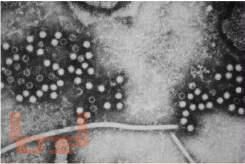

В учебном пособии на современном уровне представлены этиологическая структура, отражены особенности патогенеза, клиники, выделены опорно-диагностические признаки вирусных гепатитов с энтеральным (ВГА, ВГЕ) и парентеральным (ВГВ, ВГD, ВГC) механизмом инфицирования. С учетом последних достижений в области гепатологии представлены современные возможности диагностики и лечения острых и хронических вирусных гепатитов в зависимости от возраста, тяжести, характера течения заболевания. Даны установки по проведению противоэпидемических мероприятий в очагах инфекций, возможностях специфической профилактики, диспансеризации. Наличие в учебном пособии тестовых заданий и ситуационных задач для самоконтроля поможет студентам 5 и 6 курсов по специальности 31.05.02 – «Педиатрия» в подготовке к практическим занятиям, междисциплинарной аттестации и дальнейшей врачебной деятельности.